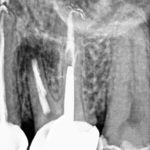

Madame X âgée de 41 ans est adressée pour avis et prise en charge de la 26 dont la reconstitution prothétique, faite récemment, lui donne satisfaction

-La dent est sensible à la palpation apicale et la percussion

-La patiente rapporte des douleurs épisodiques, spontanées d’une intensité entre 5 et 10 sur une EVA

-Un retraitement a été fait avant la pose de la prothèse avec toutes les précautions requises.

Un examen CBCT a été réalisé et la patiente se présente avec les images à la consultation